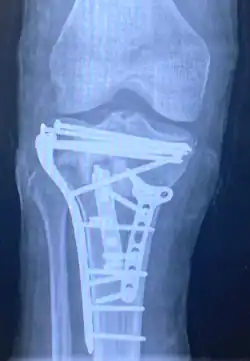

Pain may be managed with NSAIDs, opioids, and splinting.[1][2] In those who are otherwise healthy, treatment is generally by surgery.[1] Occasionally, if the bones are well aligned and the ligaments of the knee are intact, people may be treated without surgery.[2] The surgery usually involves reducing the fractured fragments of the tibia plateau to their anatomical position and fixing them in place with screws only or fixed angle anatomical plates ensuring absolute stability. Implant selection is based on the type of injury. Generally, simple or incomplete fractures (Schatzker type 1) of the plateau are compressed with 6.5mm partially threaded cancellous screws. Complex type fractures will require a plate for enhanced stability. As the tibia condyles articulate with the femur (thigh bone) to form knee joint, any incongruity in the articular surface is unacceptable as it leads to early arthritis. Prolonged immobilization of the knee joint is also not recommended which result in stiffness of the joint and difficult recovery. Following a tibial plateau fracture, the patient is at risk for arthritis. This is referred to as post-traumatic arthritis. The more displaced the joint intra-articular surface is, the more likely post-traumatic arthritis is to occur. This occurs due to injury to the joint surface cartilage. When cartilage is damaged, arthritis can occur.[15] It's currently debated what role primary total knee arthroplasty (Joint Prosthesis) plays in the treatment of tibial plateau fractures. Although accompanied with risks small studies have shown promising results.[16]

Surgery

A tibial plateau fracture requires orthopaedic surgical intervention for treatment. After X-ray and CT scans confirm fracture, Open Reduction Internal Fixation (ORIF) with medial and/or lateral plateau fixation is done. There are 5 different approaches that are most commonly used.[3]

These are: anterolateral, posteromedial, posterolateral, posterior, and dual plate fixation.

- Dual plate fixation: can be used over medial and lateral aspects of plateau; used for bicondylar plateau fractures.